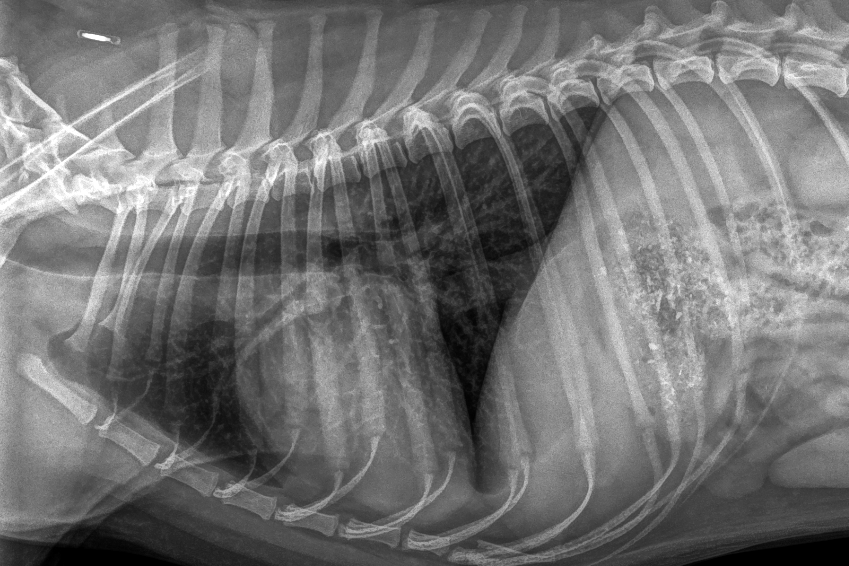

Détresse respiratoire

En réalisant une radiographie du thorax, le vétérinaire peut visualiser les appareils cardiaque et respiratoire profond. Cet examen est indiqué lorsque l'on suspecte une atteinte pulmonaire, cardiaque ou suite à un traumatisme grave.

En pratique, la radiographie est particulièrement indiquée dans l'exploration des détresses respiratoires de toute origine. L'examen permet de mettre en évidence un œdème aigu du poumon, un pneumothorax (présence d'air entre les poumons et la plèvre), une hémorragie pulmonaire ou une broncho-pneumonie comme dans les cas graves de coryza chez le chat.